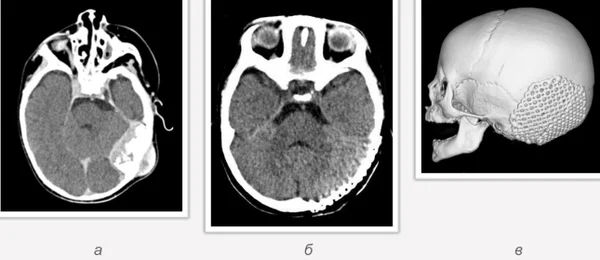

Удаление опухолей черепаВ качестве примера лечения пациентов с опухолями черепа привожу личное наблюдение пациента грудного возраста с опухолью черепа. В возрасте 1 мес. у ребёнка в затылочной области слева родителями обнаружено плотное образование диаметром 5 мм. За 3 мес. до госпитализации образование значительно увеличилось в размерах. При поступлении в возрасте 6 мес. в затылочной области слева (в проекции лямбдовидного шва) имеется безболезненное, плотное, неподвижное, бугристое образование размерами 5 х 4 х 2 см. При КТ и МРТ головы выявлена опухоль черепа в области астериона слева, обладающая преимущественно интракраниальным ростом (рис. 30 а). Ребёнку выполнено удаление опухоли черепа (рис. 30 б). Образовавшийся дефект черепа больших размеров закрыт перфорированной титановой пластиной (рис. 30 в). При наблюдении пациента в течении 2-х лет рецидива заболевания и деформации черепа не отмечалось.